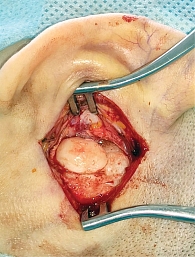

Рис. 3. Этап операции: обнажена костная стенка черепа, лоскут кожи и надкостницы фиксирован, визуализирована остеома

Хирургическое вмешательство под эндотрахеальным наркозом выполнено 06.03.2024 г. Под контролем операционного микроскопа произведен разрез мягких тканей заушной области слева, отступая около 2–3 мм от проекции опухоли. Тупо и остро новообразование выделено от мягких тканей. Новообразование костной плотности (рис. 3). Опухоль отделена от сосцевидного отростка бормашиной и долотами. Материал отправлен на гистологическое исследование. Костное ложе опухоли было обработано борами до здоровой костной ткани для предотвращения рецидива (рис. 4). Затем осмотрен наружный слуховой проход, который заполнен серными массами. После туалета уха электроотсосом отмечено, что прорастания новообразования в наружный слуховой проход нет. Барабанная перепонка серая, целая, контурирует. Разрез ушит рассасывающимся шовным материалом. Произведена тампонада комочками гемостатической губки. Повязка на заушную рану.